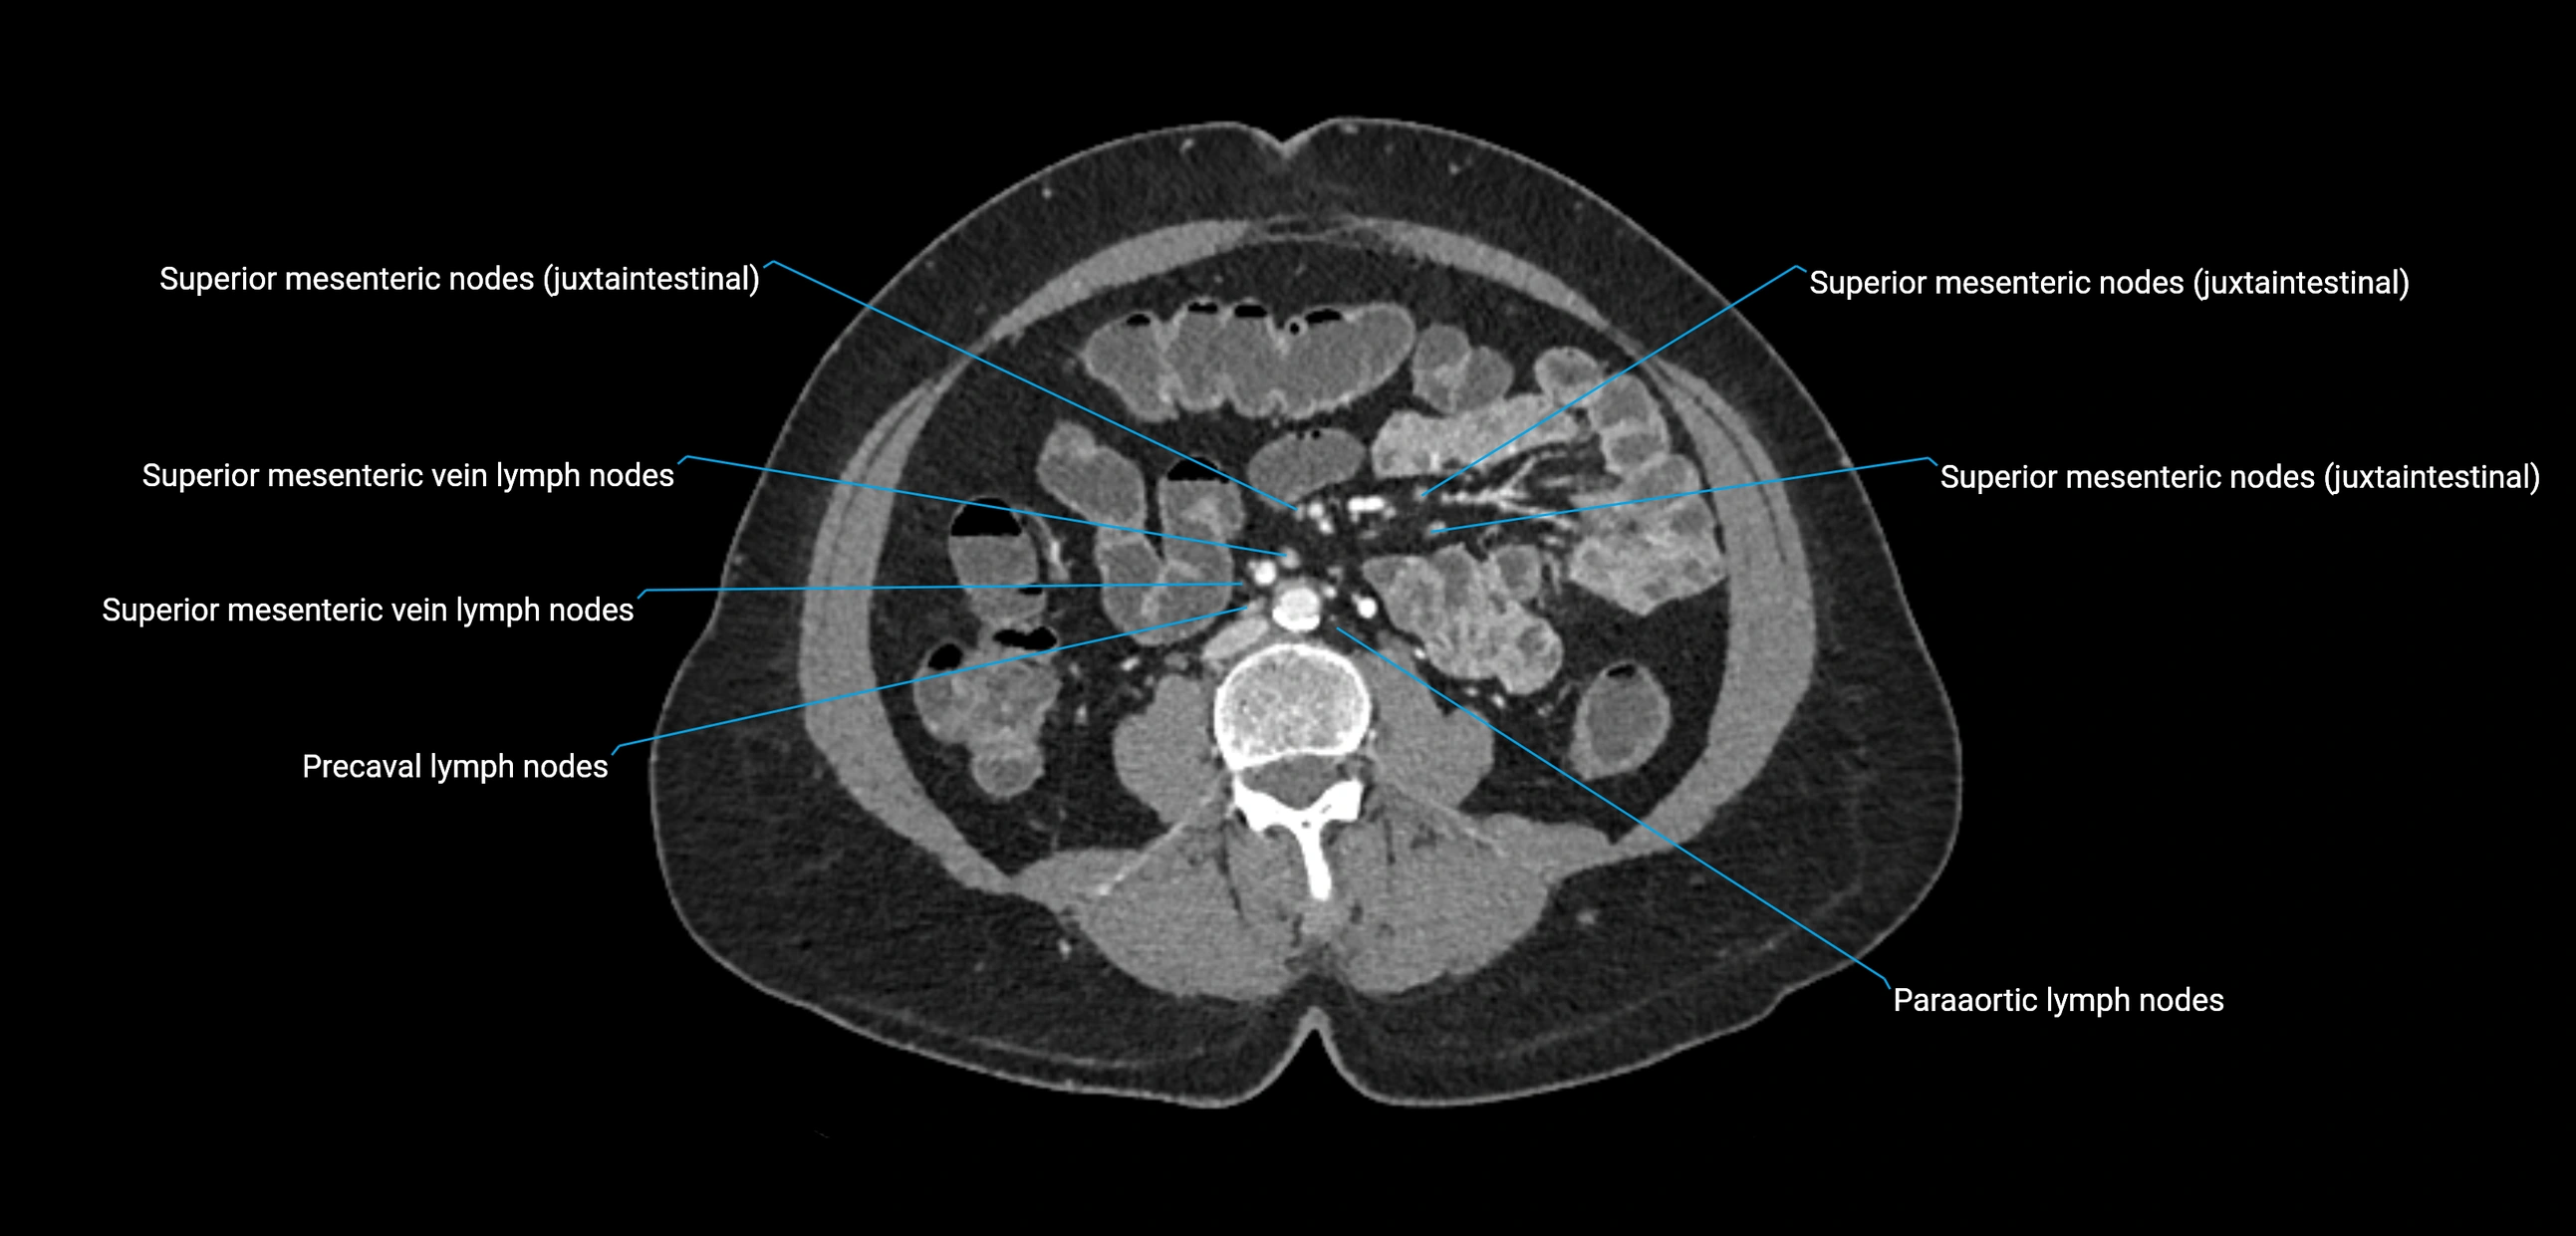

The lateral aortic lymph nodes (also called para-aortic lymph nodes) are a major group of retroperitoneal lymph nodes located along the abdominal aorta and its branches. They lie between the diaphragmatic crura superiorly and the bifurcation of the aorta at L4 inferiorly.

They are positioned on both sides of the abdominal aorta:

• Right lateral aortic nodes: adjacent to the inferior vena cava (IVC)

• Left lateral aortic nodes: lateral to the abdominal aorta

These nodes receive lymph from a wide range of abdominal and pelvic structures. Specifically, they drain lymph from the kidneys, suprarenal glands, gonads (testes/ovaries), uterus, uterine tubes, and pelvic organs, before converging into the lumbar lymphatic trunks, which terminate in the cisterna chyli → thoracic duct.

CT Appearance

CT Pre-Contrast:

• Nodes appear as soft-tissue density nodules adjacent to the aorta and IVC

• Calcification may be seen in chronic infections (e.g., tuberculosis)

CT Post-Contrast:

• Normal nodes enhance homogeneously

• Malignant nodes may show heterogeneous enhancement, central necrosis, or conglomerate formation

• Size >1 cm short axis is suspicious, though morphology and distribution are equally important